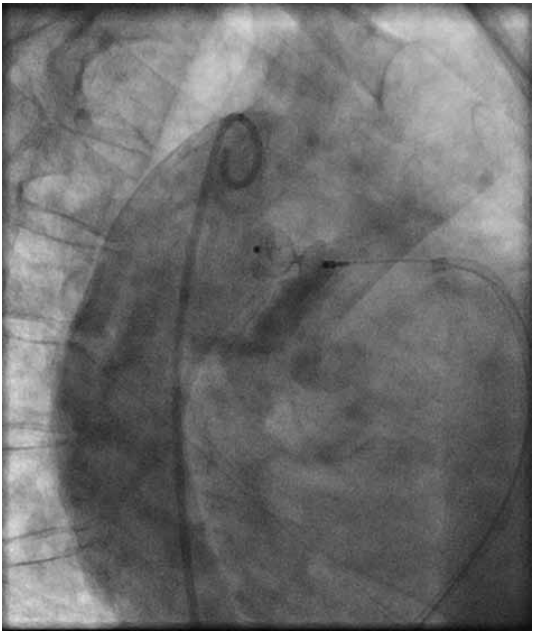

Paciente de 55 anos, feminina, vem encaminhada do Hospital de referência devido a quadro de cervicalgia associada a dor torácica esquerda de leve intensidade com piora ao esforço físico. Nega outras queixas. Tem como antecedentes: três gestações com parto cesárea sem intercorrências, ex-tabagista (carga baixa), etilista social, sedentária, diabetes mellitus não insulino dependente, osteoporose e hipertensão arterial sistêmica.

Ao exame físico: bom estado geral. FC = 75 bpm; FR = 20 irpm; PA = 160 x 70 mmHg; Saturação periférica de O2 em ar ambiente = 97% em membro superior direito e 98% em membro inferior direito. Presença de bulhas rítmicas, normofonéticas, em dois tempos e com sopro contínuo em região infraclavicular esquerda. Pulsos periféricos presentes e de amplitude aumentada.

Com base nesta figura de cateterismo cardíaco, qual a cardiopatia congênita diagnosticada?